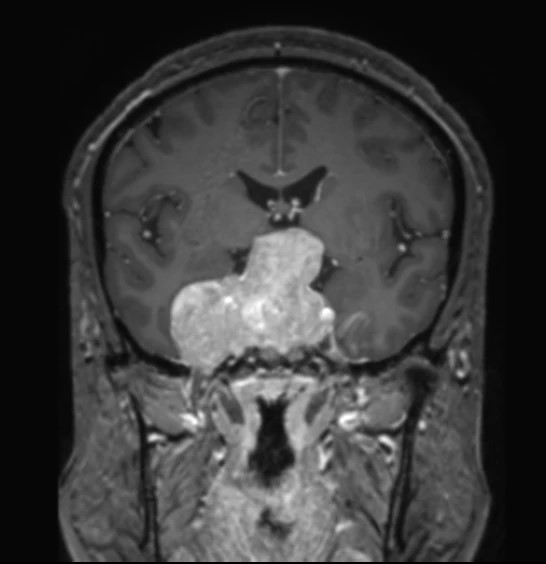

Фото Снеговики бывают разные, но смысл симптома при аденоме гипофиза от этого не меняется: когда опухоль растёт вверх, она протискивается черезу дуральную селлярную диафрагму и в этом месте на ней явственно определяется поясок. Это, как утверждается, достаточно надёжный дифференциально диагностический признак (точность порядка 94-96%) именно аденомы гипофиза, а не какой-то другой опухоли данного расположения.